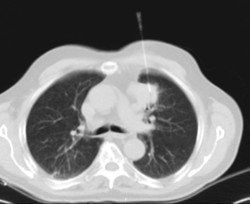

Prova diagnòstica que consisteix en obtenir imatges del tòrax d'alta definició anatòmica (pulmons, cor, mediastí, grans vasos, caixa toràcica, etc. ) mitjançant l'ús d'un equip de TC (Tomografia Computeritzada). Aquestes imatges s'estudien posteriorment en una estació de treball que permet reconstruccions bidimensionals en diferents plànols de l'espai i també reconstruccions 3D (volumètriques). Alguns estudis requereixen l'ús de contrast iodat per millorar la definició de les imatges. - Angio –TC Aorta toràcica

Prova diagnòstica que consisteix en l'estudi de les artèries pulmonars mitjançant l'ús d'un equip de TC (Tomografia Computeritzada) per obtenir imatges bi i tridimensionals. En aquest estudi és imprescindible l'ús de contrast iodat que permet una millor definició anatòmica. Aquesta prova està principalment indicada en els casos de sospita de tromboembòlia pulmonar (TEP) per descartar o confirmar la presència de coàguls sanguinis a l'interior de les artèries. - TC Tòrax d'alta resolució